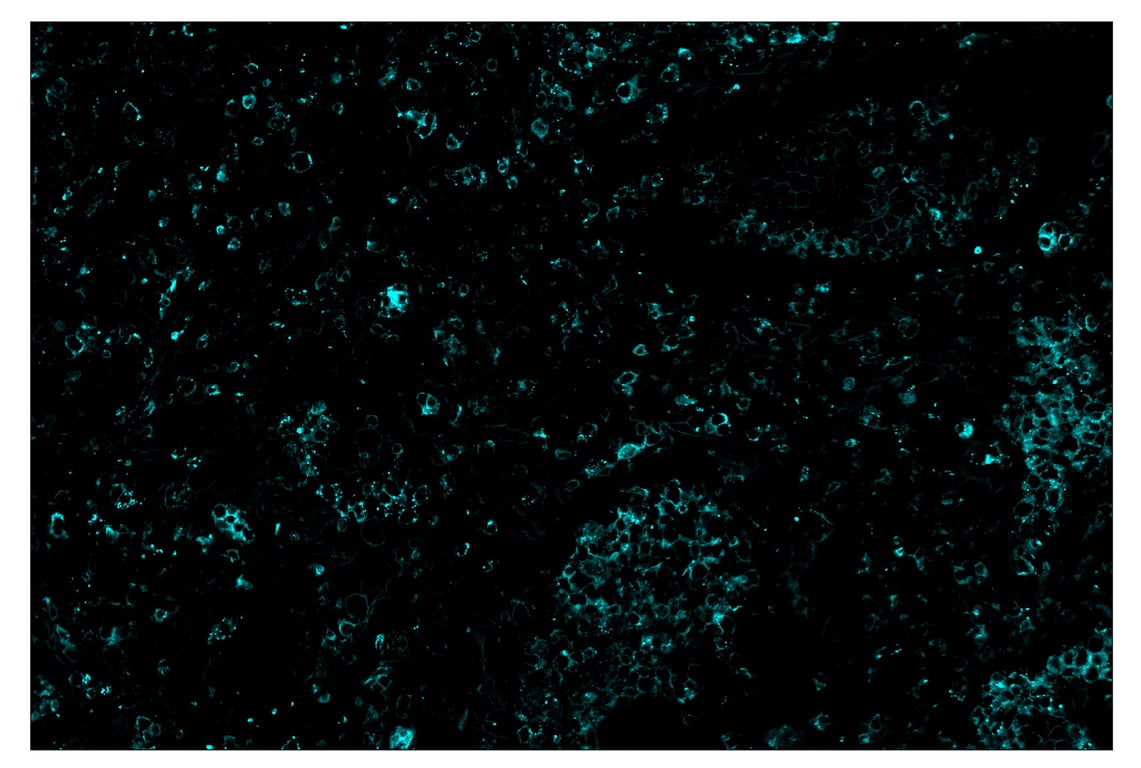

SignalStar™ immunohistochemical analysis of paraffin-embedded human non-small cell lung carcinoma using TIM-3 (D5D5R™) & CO-0010-750 SignalStar™ Oligo-Antibody Pair #34802 (cyan). All fluorophores have been assigned a pseudocolor, as indicated. Staining was performed on the BOND RX by Leica Biosystems.

Immunohistochemistry Image 5: TIM-3 (D5D5R<sup>™</sup>) & CO-0010-750 SignalStar<sup>™</sup> Oligo-Antibody Pair